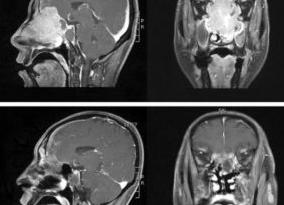

Магнитно-резонансная томография представляет собой новейшую методику диагностирования патологий. Ее используют для осмотра внутренних органов, систем и сосудов. МРТ нередко применяют при патологиях, связанных с ЛОР-органами, например, для обследования пазух носа. Обследование носовых пазух может производиться как при полноценном исследовании головы, так и отдельно. МРТ используют достаточно редко, это связано с тем, что более простые и доступные процедуры, как КТ и рентген носовых пазух, позволяют диагностировать заболевания носовых полостей достаточно точно. МРТ незаменима в сложных случаях, например, при наличии у пациента патологических процессов в области носоглотки, при осложненных клиновидных и решетчатых пазухах. Подробнее ...